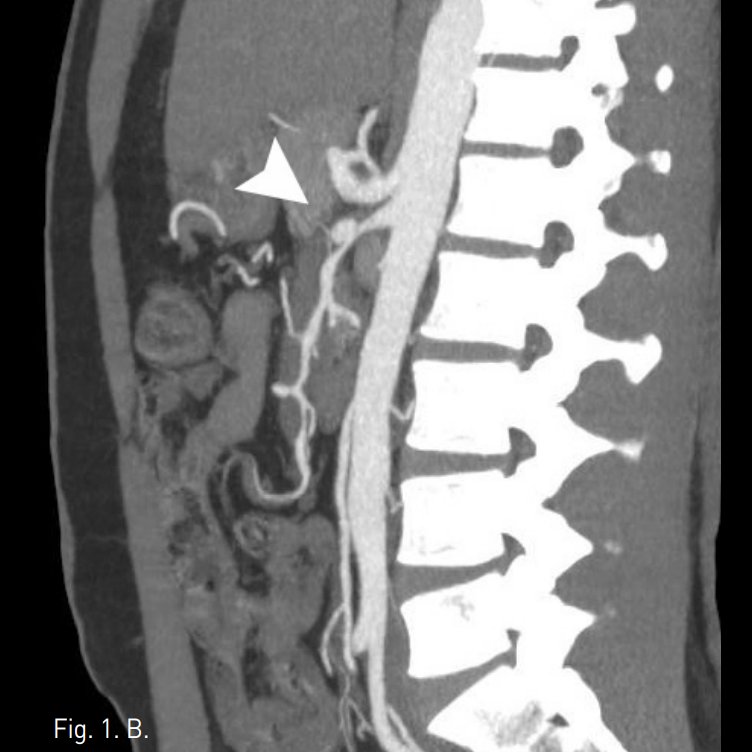

시술 전 CTA상 상장간막동맥 근위부에 직경 10mm 크기의 박리성동맥류가 확인되었고, 상장간막동맥은 벽내혈종으로 인해 혈관 직경은 12mm로 커지고 내강은 3mm로 협착소견을 보였다(Fig. 1A-C).

Fig. 1

A-C. Initial CT scan (A) shows dilated SMA with circumferential intramural hematoma and stenotic true lumen (arrow). Sagittal reconstructed MIP image (B) and volume rendered 3D CTA (C) show 1cm sized dissecting aneurysm (arrow hed) at proximal SMA and diffuse narrowing of true lumen.